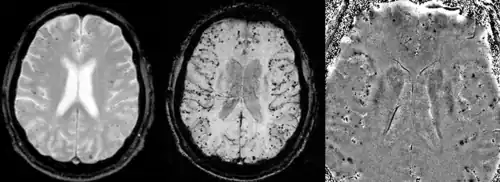

Gradient recalled echo (GRE) imaging is the conventional way to detect hemorrhage in CAA, however SWI is a much more sensitive technique that can reveal many micro-hemorrhages that are missed on GRE images.[7] A conventional gradient echo T2*-weighted image (left, TE=20 ms) shows some low-signal foci associated with CAA. On the other hand, an SWI image (center, with a resolution of 0.5 mm x 0.5 mm x 2.0 mm, projected over 8mm) shows many more associated low-signal foci. Phase images were used to enhance the effect of the local hemosiderin build-up. An example phase image (right) with yet higher resolution of 0.25 mm x 0.25 mm x 2.0 mm shows a clear ability to localize multiple CAA-associated foci.